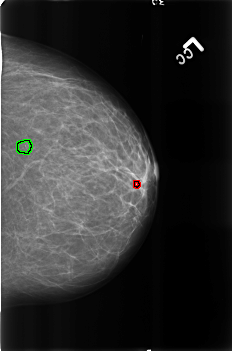

B_3165_1.LEFT_CC

LEFT_CC LINES 4552 PIXELS_PER_LINE 3016 BITS_PER_PIXEL 12 RESOLUTION 50 OVERLAY

FILE: B_3165_1.LEFT_CC.OVERLAY

TOTAL_ABNORMALITIES 2

ABNORMALITY 1

LESION_TYPE CALCIFICATION TYPE LUCENT_CENTER DISTRIBUTION N/A

ASSESSMENT 2

SUBTLETY 4

PATHOLOGY BENIGN_WITHOUT_CALLBACK

TOTAL_OUTLINES 1

BOUNDARY

ABNORMALITY 2